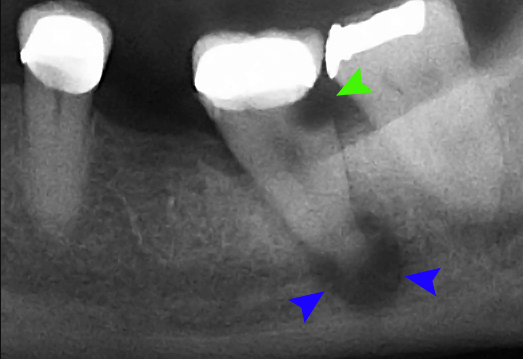

Cas clinique n°2 — Gangrène fermée avec parodontite apicale chronique

Présentation Fatima, 34 ans. Gêne intermittente à la mastication sur 35 depuis 3 mois. Pas de douleur spontanée, pas de gonflement.

Problématique Test de vitalité négatif. Image radioclaire péri-apicale de 5 mm. Diagnostic : gangrène fermée avec granulome péri-apical.

Point clé Une gangrène fermée peut évoluer silencieusement des mois. Toute image radioclaire péri-apicale impose un test de vitalité.